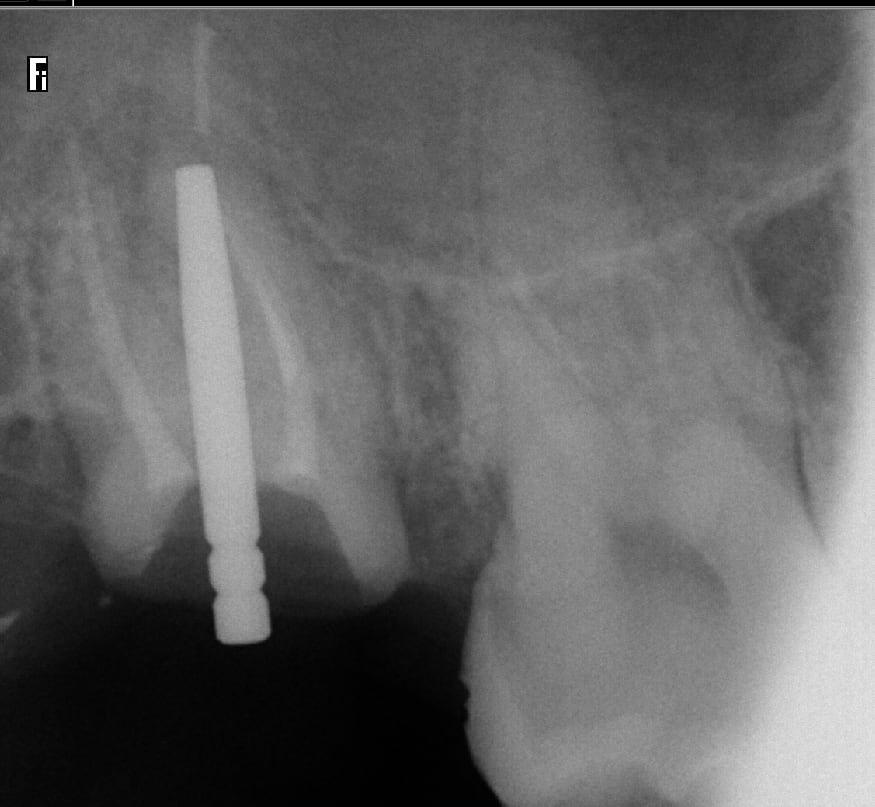

Bon petit cas de ce matin. Reprise de traitement endo sur 17, Préparation coronoradiculaire infragingivale.

Retraction gingivale et empeinte optique. Bonne lisibilité des limites dans l'empreinte optique mais j'ai fais un silicone pour tester la fonction qui a très bien marché.

On s'éclate! https://www.meditlink.com/webViewer?shareKey=f58f58e8-4d35-4a29-b8f8-82b6dccf92b7